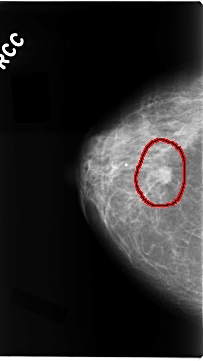

C_0100_1.RIGHT_CC

RIGHT_CC LINES 4688 PIXELS_PER_LINE 2632 BITS_PER_PIXEL 12 RESOLUTION 50 OVERLAY

FILE: C_0100_1.RIGHT_CC.OVERLAY

TOTAL_ABNORMALITIES 1

ABNORMALITY 1

LESION_TYPE MASS SHAPE IRREGULAR MARGINS SPICULATED

ASSESSMENT 5

SUBTLETY 5

PATHOLOGY MALIGNANT

TOTAL_OUTLINES 1

BOUNDARY